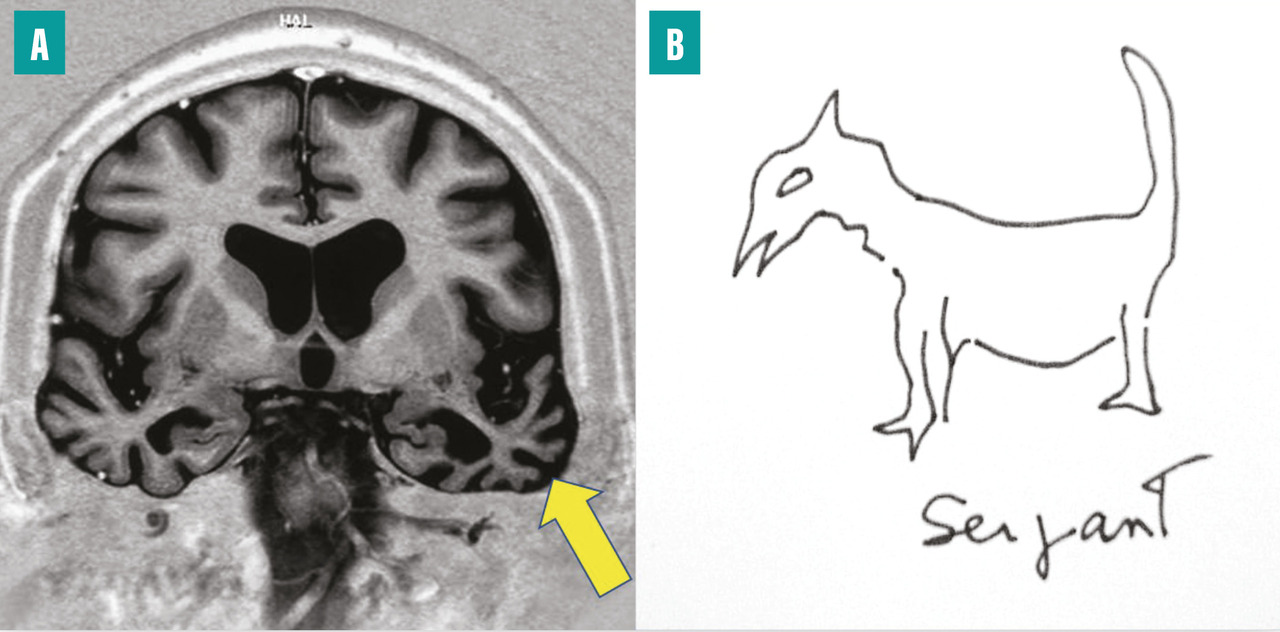

Ce tableau est dû à une maladie neurodégénérative qui touche le néocortex temporal, singulièrement le cortex périrhinal et le pôle temporal antérieur, de façon asymétrique (fig. 5A ). Le pôle temporal joue le rôle de nœud de connexion pour accéder à la mémoire sémantique, c’est-à-dire à toutes les connaissances générales distribuées dans le cerveau. Le tableau est singulier : le malade garde une bonne mémoire au jour le jour et sa mémoire autobiographique, mais il perd des pans entiers de son savoir (sur les animaux, les outils, la géographie, etc.). Le langage est fluide, mais il existe un manque du mot, masqué par des circonlocutions ou des mots valises (truc, machin), des mots génériques. Les mots ne sont non seulement pas trouvés, mais ils ne sont plus non plus associés à leur sens (fig. 5B ). L’écriture se fait avec des erreurs phonologiquement correctes (« agraphie de surface »). Les patients restent assez autonomes de nombreuses années, dans leur environnement habituel. C’est une des raisons pour lesquelles on tend à renoncer au terme de démence sémantique au profit de celui d’« aphasie progressive, variant sémantique », bien que la clé des déficits soit un trouble de la mémoire. Ce tableau est une des formes cliniques des dégénérescences lobaires fronto-temporales (DLFT). Sur le plan neuropathologique, on observe le plus souvent des inclusions neuronales dites TDP-43 de type C.9